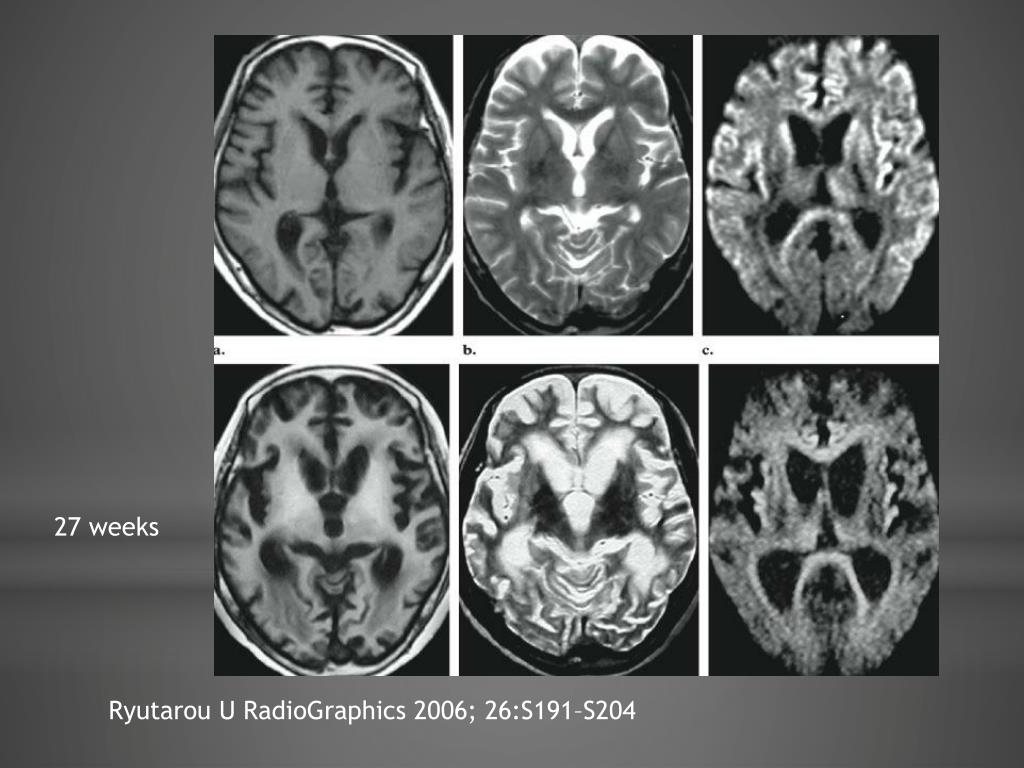

16. 27 weeks RyutarouU RadioGraphics2006; 26:S191–S204